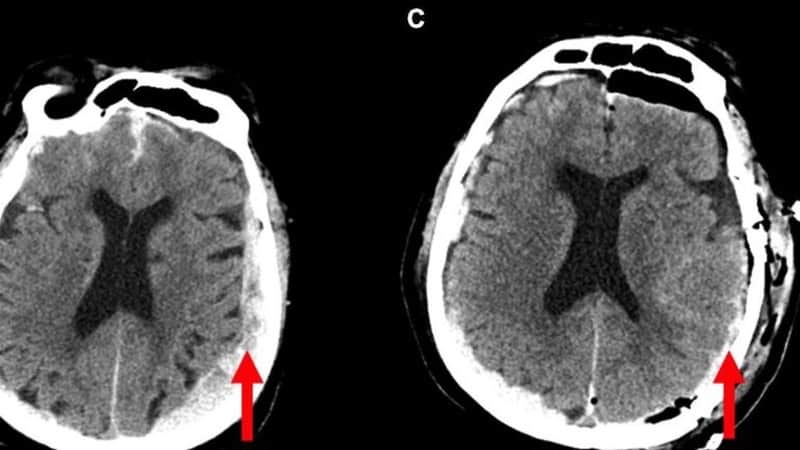

Naučnici snimili: Šta se događa u glavi prije umiranja